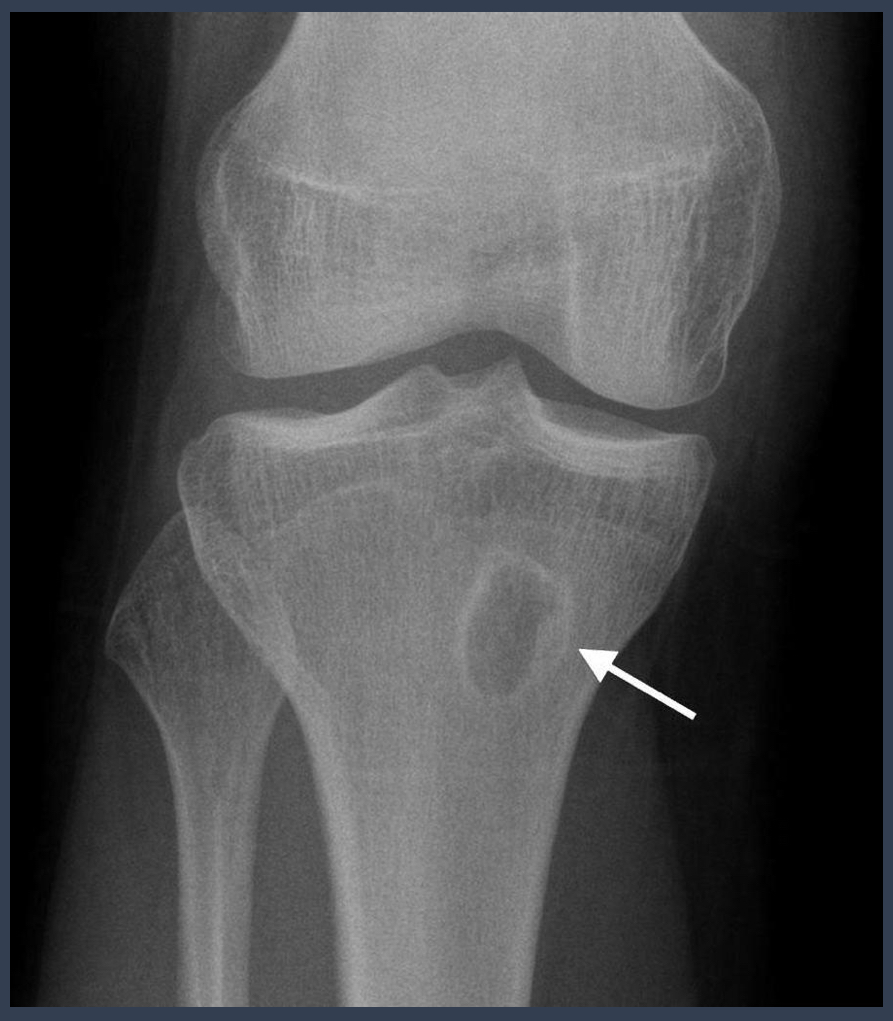

what is this condition?

septic arthritis?

what is noted by the arrow here?

loss of joint space

what should be the ratio of the femoral-acetabular joint?

1:1:2

what is this?

septic arthritis

joint space loss

bone destruction

rapid over several weeks